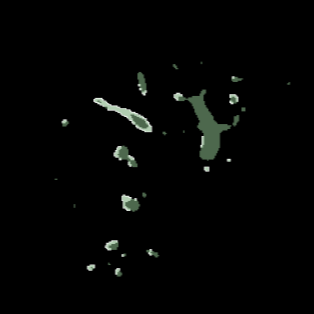

Manually segmenting the hepatic vessels from Computer Tomography (CT) is far more expertise-demanding and laborious than other structures due to the low-contrast and complex morphology of vessels, resulting in the extreme lack of high-quality labeled data. Without sufficient high-quality annotations, the usual data-driven learning-based approaches struggle with deficient training. On the other hand, directly introducing additional data with low-quality annotations may confuse the network, leading to undesirable performance degradation. To address this issue, we propose a novel mean-teacher-assisted confident learning framework to robustly exploit the noisy labeled data for the challenging hepatic vessel segmentation task. Specifically, with the adapted confident learning assisted by a third party, i.e., the weight-averaged teacher model, the noisy labels in the additional low-quality dataset can be transformed from "encumbrance" to "treasure" via progressive pixel-wise soft-correction, thus providing productive guidance. Extensive experiments using two public datasets demonstrate the superiority of the proposed framework as well as the effectiveness of each component.